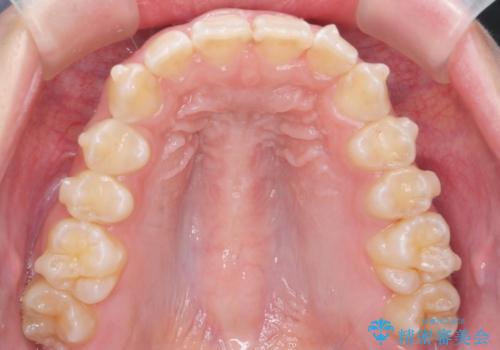

前歯の並び インビザライン 非抜歯で 深いかみ合わせの治療

- 前歯の並びを気にして来院。

上の前歯が内側に倒れこんでいました。

インビザラインで前歯の並びを整えています。

前歯の重なりが大きいいわゆる過蓋咬合を呈していましたが、ある程度適正な重なりにすることができました。